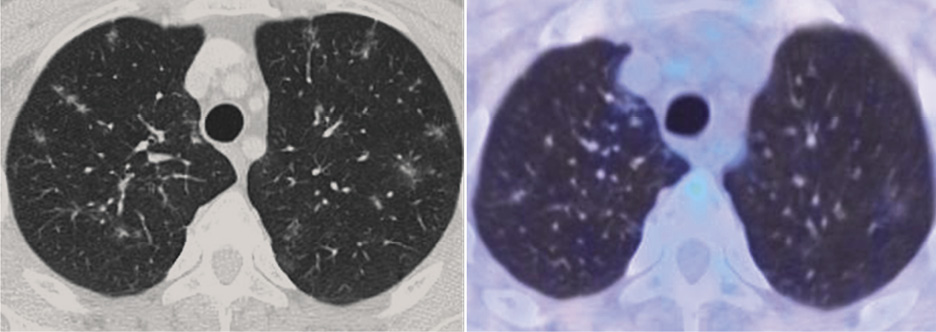

В легких с обеих сторон полисегментарно выявлены многочисленные очаговые образования и участки снижения пневматизации по типу матового стекла различных форм и размеров, часть из которых с повышенной метаболической активностью ФДГ специфического характера. Контрольный очаг в доле S3 правого легкого, размером до 6 мм, SUVmax 2,73 (рис. 5).

Рис. 5. Больной С., 43 года. На аксиальной КТ- и совмещенной ПЭТ/КТ-проекциях в легких с двух сторон определяются многочисленные очаговые уплотнения и участки сниженной пневматизации по типу матового стекла с метаболической активностью ФДГ, SUVmax 2,73.